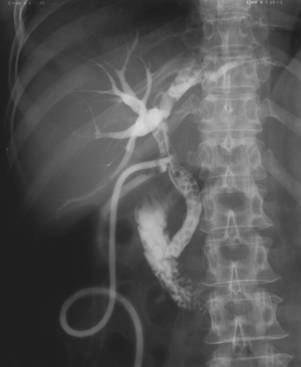

Fig. 56 – Calculi coledocieni reziduali (colangiografie pe tub Kerr – multiple imagini lacunare bine delimitate situate pe canalul coledoc)